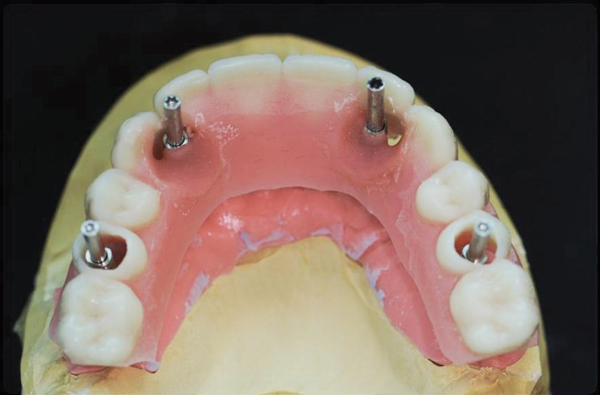

An important advantage of this approach is the ability to simulate bone reduction on the models and verify the presence of 15 mm to 17 mm and 13 mm to 15 mm of required inter-occlusal space for maxillary and mandibular restorations, respectively. This creates a platform for a diagnostic wax-up of the proposed dental rehabilitation and fabrication of wax prosthesis try-ins when necessary. Finally, a modified All-on-4 provisional prosthesis surgical and restorative guide developed by the authors for restoration-driven surgery and simplified restorative procedures is fabricated (Figure 2 through Figure 8).

Fig 5. Bone reduction model surgery performed in mandibular arch to create 13 mm to 15 mm of inter-occlusal space required for the mandibular All-on-4 provisional restoration.

Figure 5